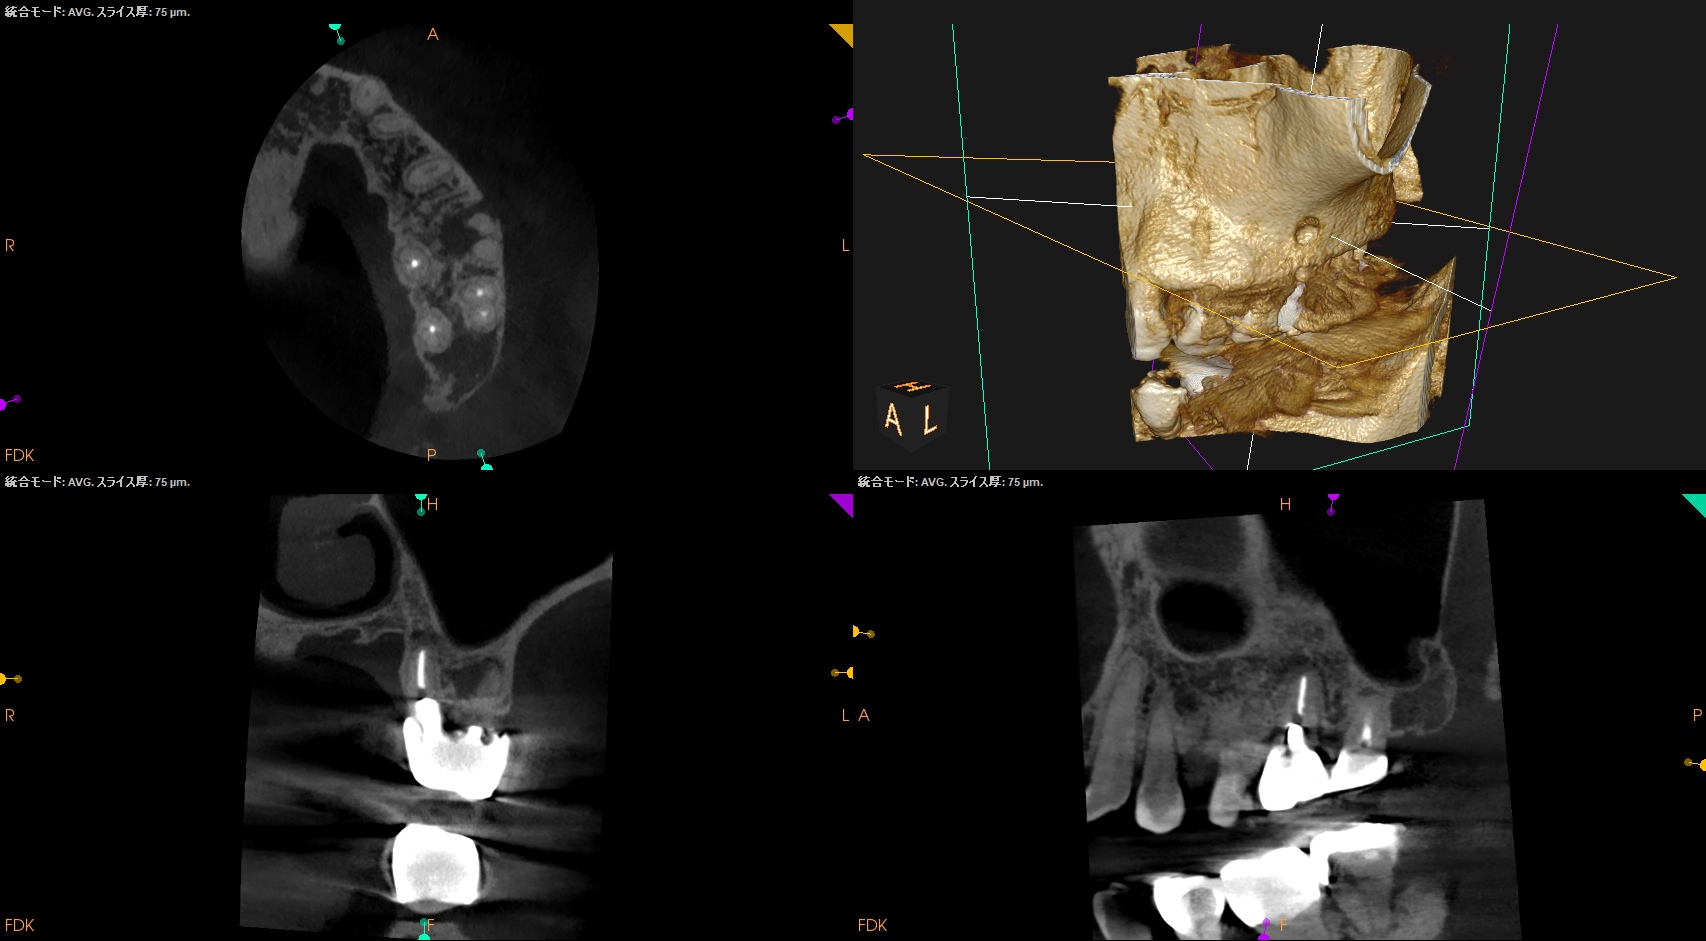

Pulp Dx: Previously treated

Periapical Dx: Chronic apical abscess

Recommended Tx: Apicoectomy

術後にPA, CBCTを撮影した。